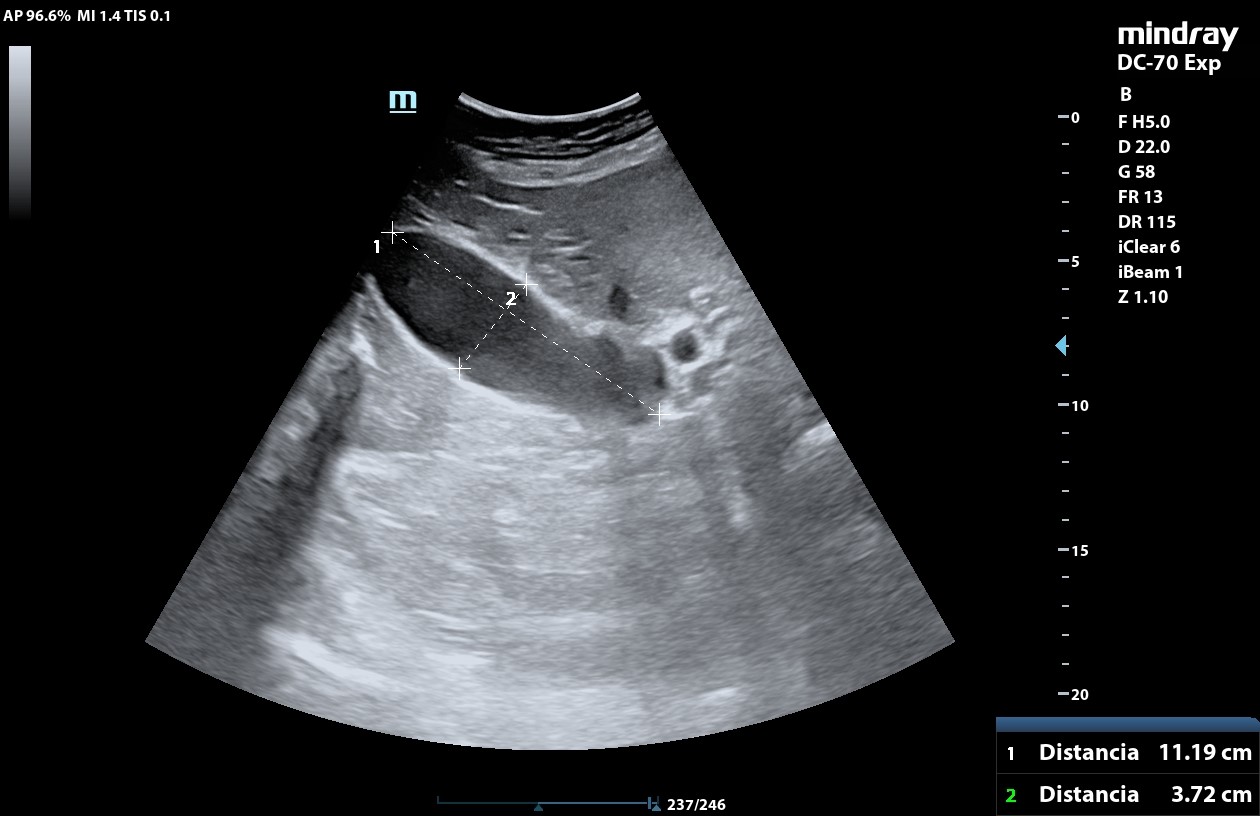

• POCUS: aumento tamaño de la vesícula biliar, eje longitudinal mayor de 11,19 cm, con pared vesicular engrosada de 0,43 cm y dilatación de la vía biliar. En su interior hay material ecogénico que no deja sombra posterior, compatible con barro biliar. No objetivo páncreas por interposición de gas intestinal. No presencia de líquido libre.